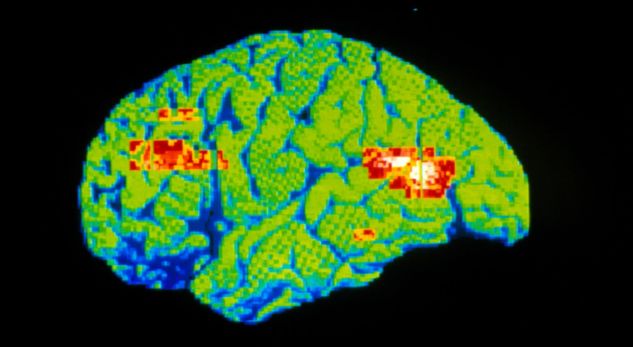

Mekanizmi i veprimit të kësaj substance mbështetet në aftësinë e targetimin të receptorëve të acidit glutemik në tru, me ç’rast krijon një ndërveprim më intensiv në mes qelizave neurale të trurit – shkruan Independent, transmeton Gazeta Express.